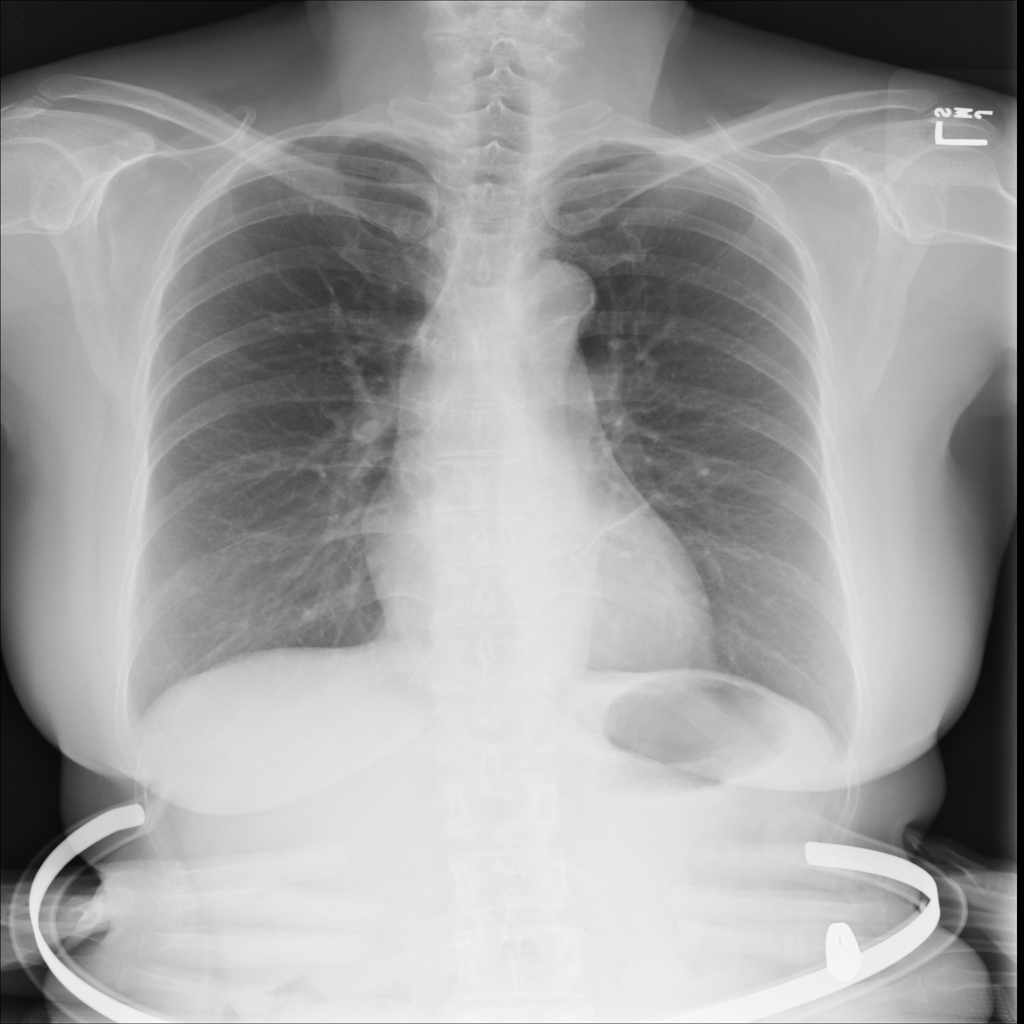

PAT-C77C · IMG-003Fibrosis

PAT-C77C · IMG-003

PA